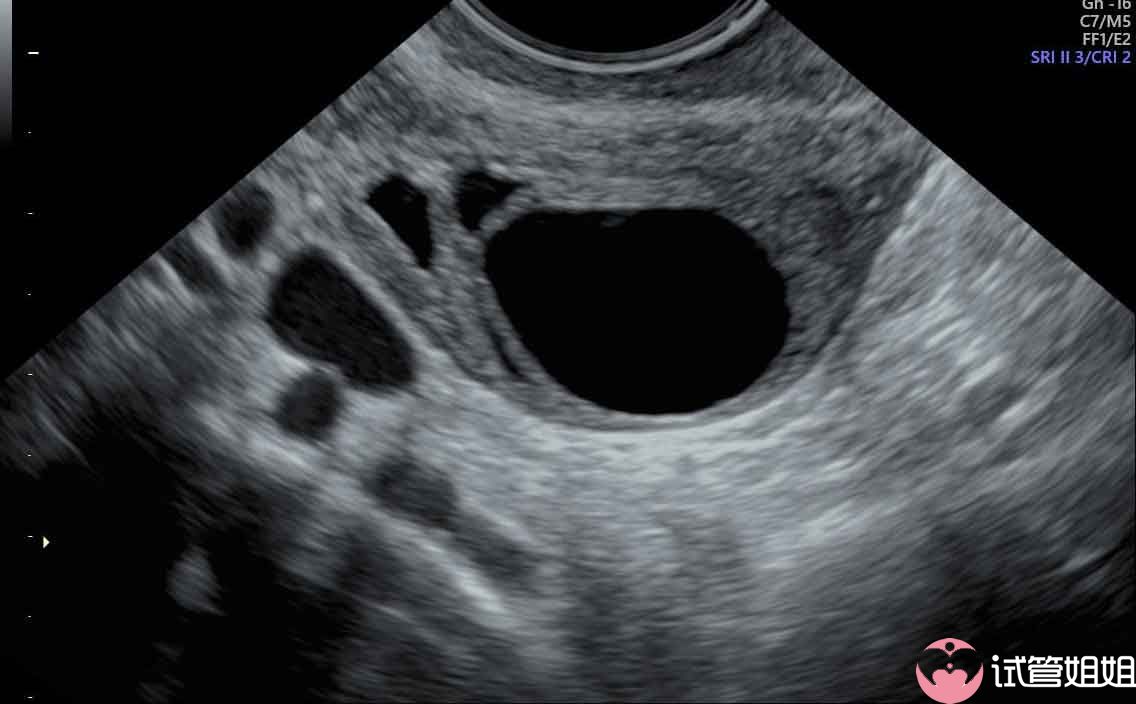

这些症状通常在停止用药后会逐渐消失。虽然激素治疗可能会对女性的身体造成一定的影响,但医生会在治疗过程中根据患者的具体情况进行调整,以确保患者的身体状况得到最佳的保障。二.胚胎移植的过程:三代试管婴儿的胚胎移植过程相对简单,通常不需要开刀。在移植过程中,医生会将培养好的胚胎放入子宫内,以期与女性的子宫内膜结合。